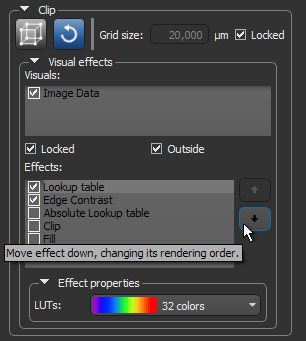

In addition to letting you interactively clip image data, regions of interest, multi-ROIs, and meshes, additional visual effects can also be applied to the clipped region of selected objects, such as look-up table functions, edge contrast, and window leveling. Visual effects, which are available in the Visual effects box shown below, can also be applied to shapes such as boxes, capsules, cylinders, and spheres (see Shapes).

Visual effects for clips and shapes

For a selected effect, the Effects box displays the properties based on the nature of the effect and includes controls, such as sliders, menus, and color swatches, that you can use to change its properties. You should note that multiple effects can be applied simultaneously (see Working with Multiple Effects).

Visual effects can be applied either to the inside or outside of the clipped region or shape. Check the Outside option to apply the effect to the data of selected visuals that is exterior to the region. Leave the Outside option unchecked to apply the effect to the data of selected visuals inside the clipped region or shape.